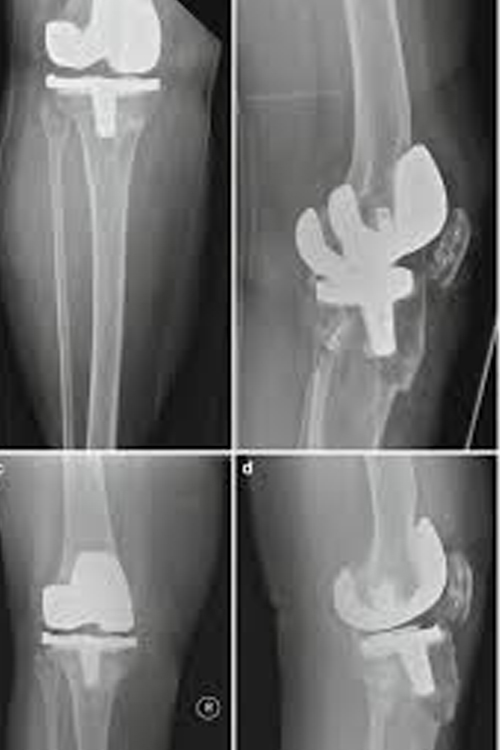

Periprosthetic fractures occur around an existing joint implant, such as:

• Knee replacement